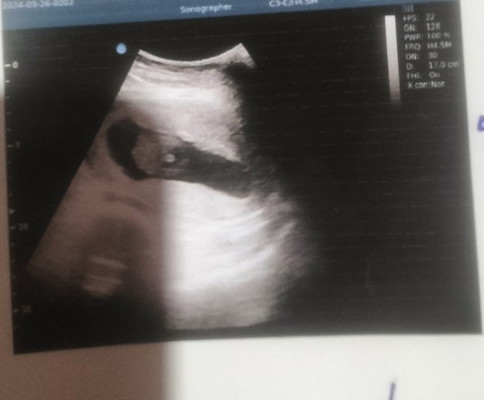

ผู้ชายใช่ไหมคะแม่ๆช่วยดูหน่อยค่ะ

ซาวด์ตอนอายุครรภ์16สัปดาห์ค่ะ

น่าจะชายค่ะแม่ แต่ถ้าจะชัว รอน้องโตกว่านี้นิดหนึ่ง คงชัดแจ๋วเลยค่ะ